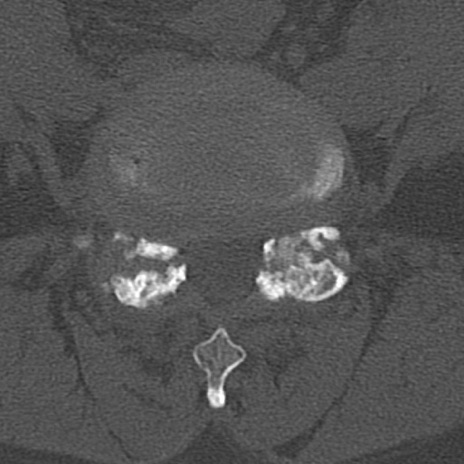

腰椎CT

横断像と矢状断像